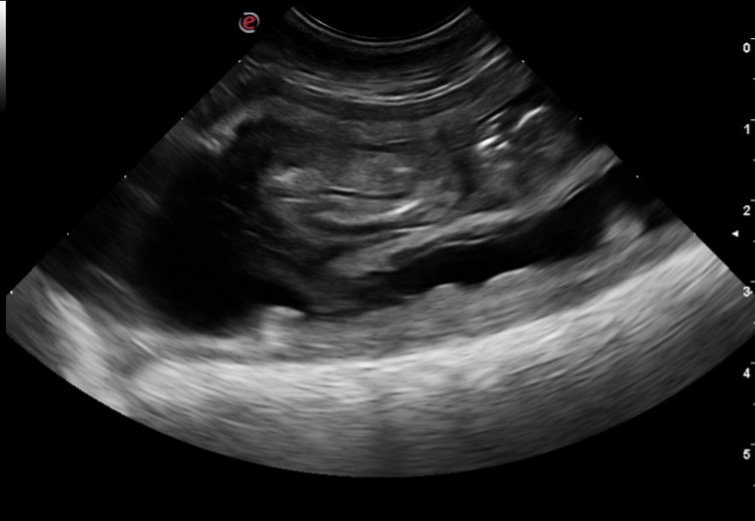

7 maart heeft Tess de echo gehad. Ze is drachtig! Er zijn 3 vruchtzakjes duidelijk te zien. Het kan zijn dat er een vruchtje dubbel zit. De dierenarts zegt dat er 3-5 puppy's geboren gaan worden. Een klein nestje dus. Dat betekent dat de puppylijst nu wel vol is